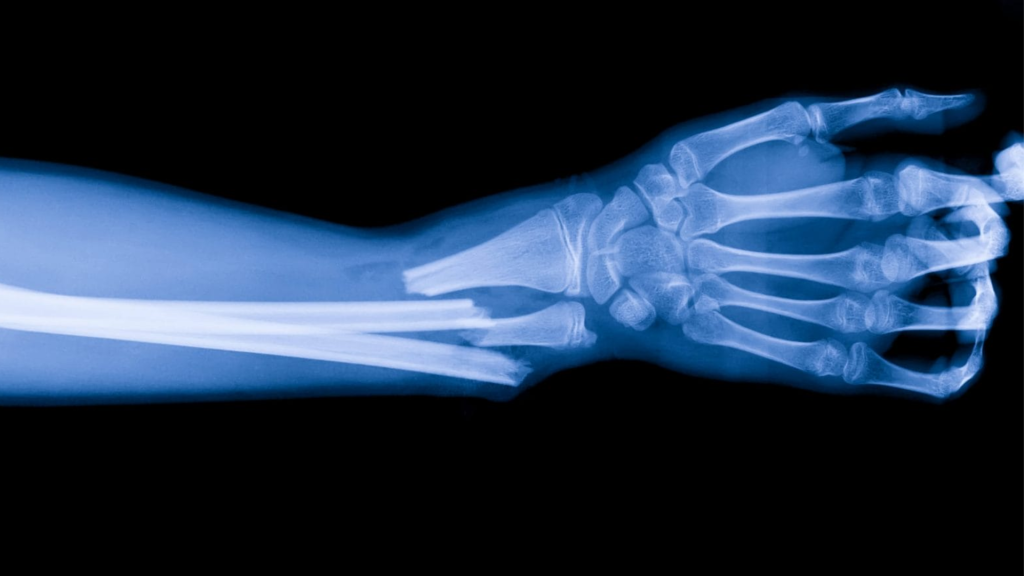

Diagnosticare deviatii axiale

Deviațiile axiale la copii – cauze, simptome și tratament

Deviațiile axiale la copii sunt o problemă comună care poate afecta sănătatea oaselor și a articulațiilor. Acestea se referă la alinierea incorectă a oaselor sau articulațiilor în raport cu axa corpului și pot cauza complicații dacă nu sunt tratate corespunzător.